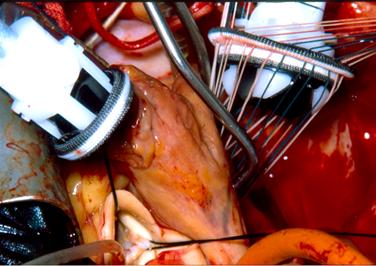

TROMBOSI DI PROTESI MECCANICA MONODISCO

Le protesi valvolari biologiche sono costruite utilizzando valvole

cardiache aortiche porcine fissate in glutaraldeide oppure ritagliando il pericardio bovino

per ottenere tre lembi che poi vengono suturati per ottenere una g neo-valvola g. Queste valvole

richiedono una terapia anticoagulante solo per un breve periodo (in genere 3

mesi) in quanto il sangue non tende a coagulare a contatto con questi tessuti.